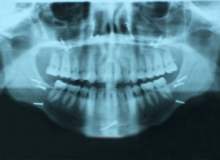

Kırık Çene Kemiği

Kırık çene kemiği yaygın bir yüz yaralanmasıdır. Sadece burun daha fazla sayıda kırılır. Çene kırığı insan vücudundaki en yaygın onuncu kemik kırılmasıdır. Kemik kırıkları genellikle çene kemiğine doğrudan uygulanan bir kuvvetin veya çarpmanın sonucu